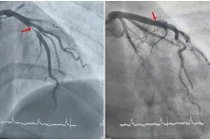

Bệnh nhân ngay lập tức được thăm khám, làm điện tim, xét nghiệm, siêu âm tim và được chẩn đoán mắc bệnh nhồi máu cơ tim cấp – một tình trạng cực kỳ nguy hiểm nếu không xử trí kịp thời. Ê-kíp khẩn trương can thiệp mạch vành bằng hệ thống máy Philips hiện đại hàng đầu thế giới.

Ngay sau thủ thuật, tình trạng đau tức ngực và khó thở của bệnh nhân giảm rõ rệt. Mạch máu được tái thông hiệu quả, chức năng tim được bảo tồn tốt.